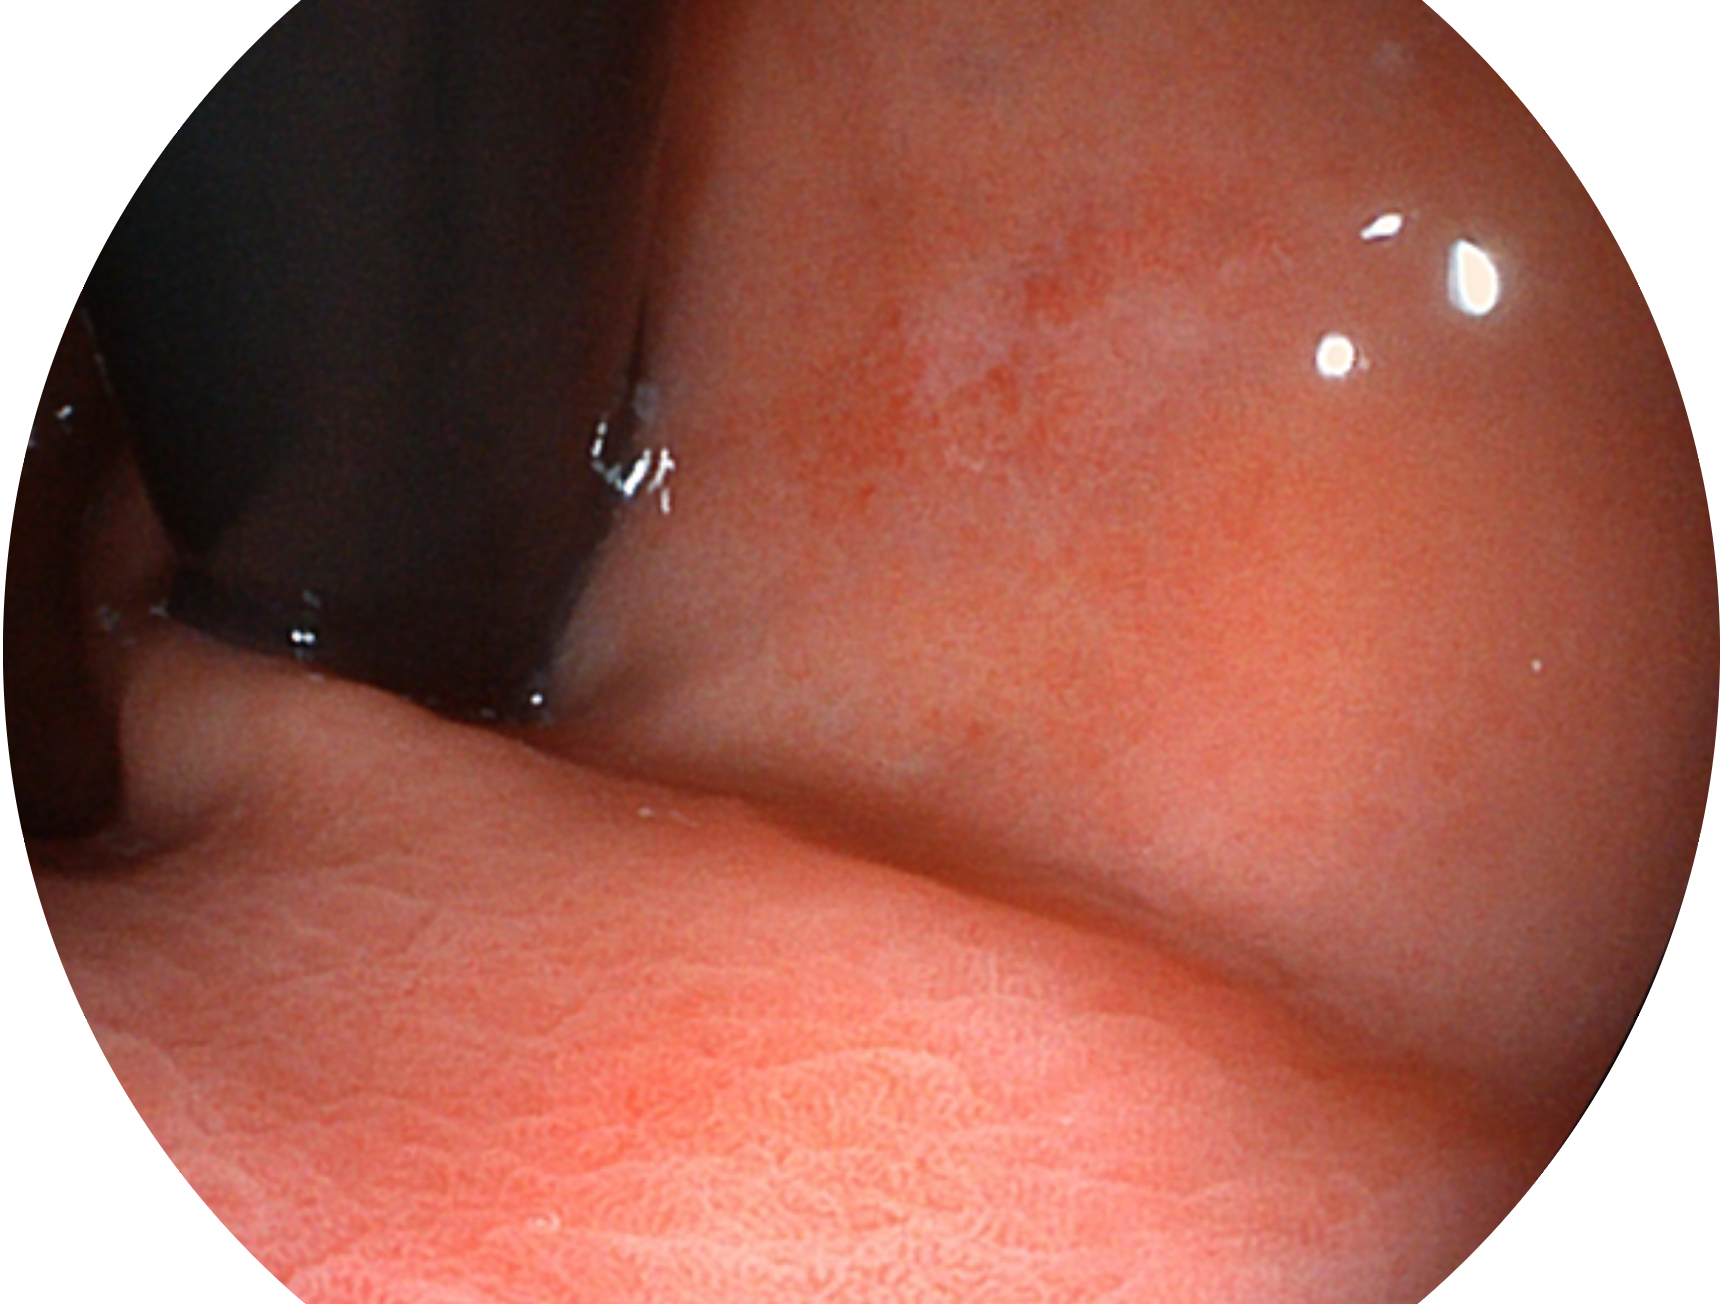

開立新開發(fā)的內(nèi)鏡染色技術(shù),主要是基于多波長LED 光源的開發(fā),VLS-55Q 四波長LED 光源是由四個不同顏色的LED光按照相應(yīng)照明模式所規(guī)定的特定發(fā)光比例進(jìn)行合束后形成,合束后形成的照明光的光譜由紅光、綠光、藍(lán)光及藍(lán)紫光這四個不同的波段范圍構(gòu)成。具有更高光譜自由度,通過光譜比例的控制,實現(xiàn)了聚譜成像技術(shù),英文全稱為“Spectral Focused Imaging, SFI”,縮寫為“SFI”和光電復(fù)合染色成像技術(shù),英文全稱為“Versatile Intelligent Staining Technology, VIST”,縮寫為“VIST”。